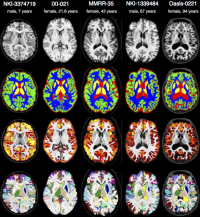

Within this project, clinically acquired magnetic resonance imaging (MRI) brain data of the past years is processed retrospectively. Using these data the primary task is to create a brain template with the Advanced Normalization Tools (ANTs) which will serve as a reference in diagnosis in neurodegenerative and psychiatric diseases. Beyond this, further tasks may vary depending on the individual skillset and type of work.